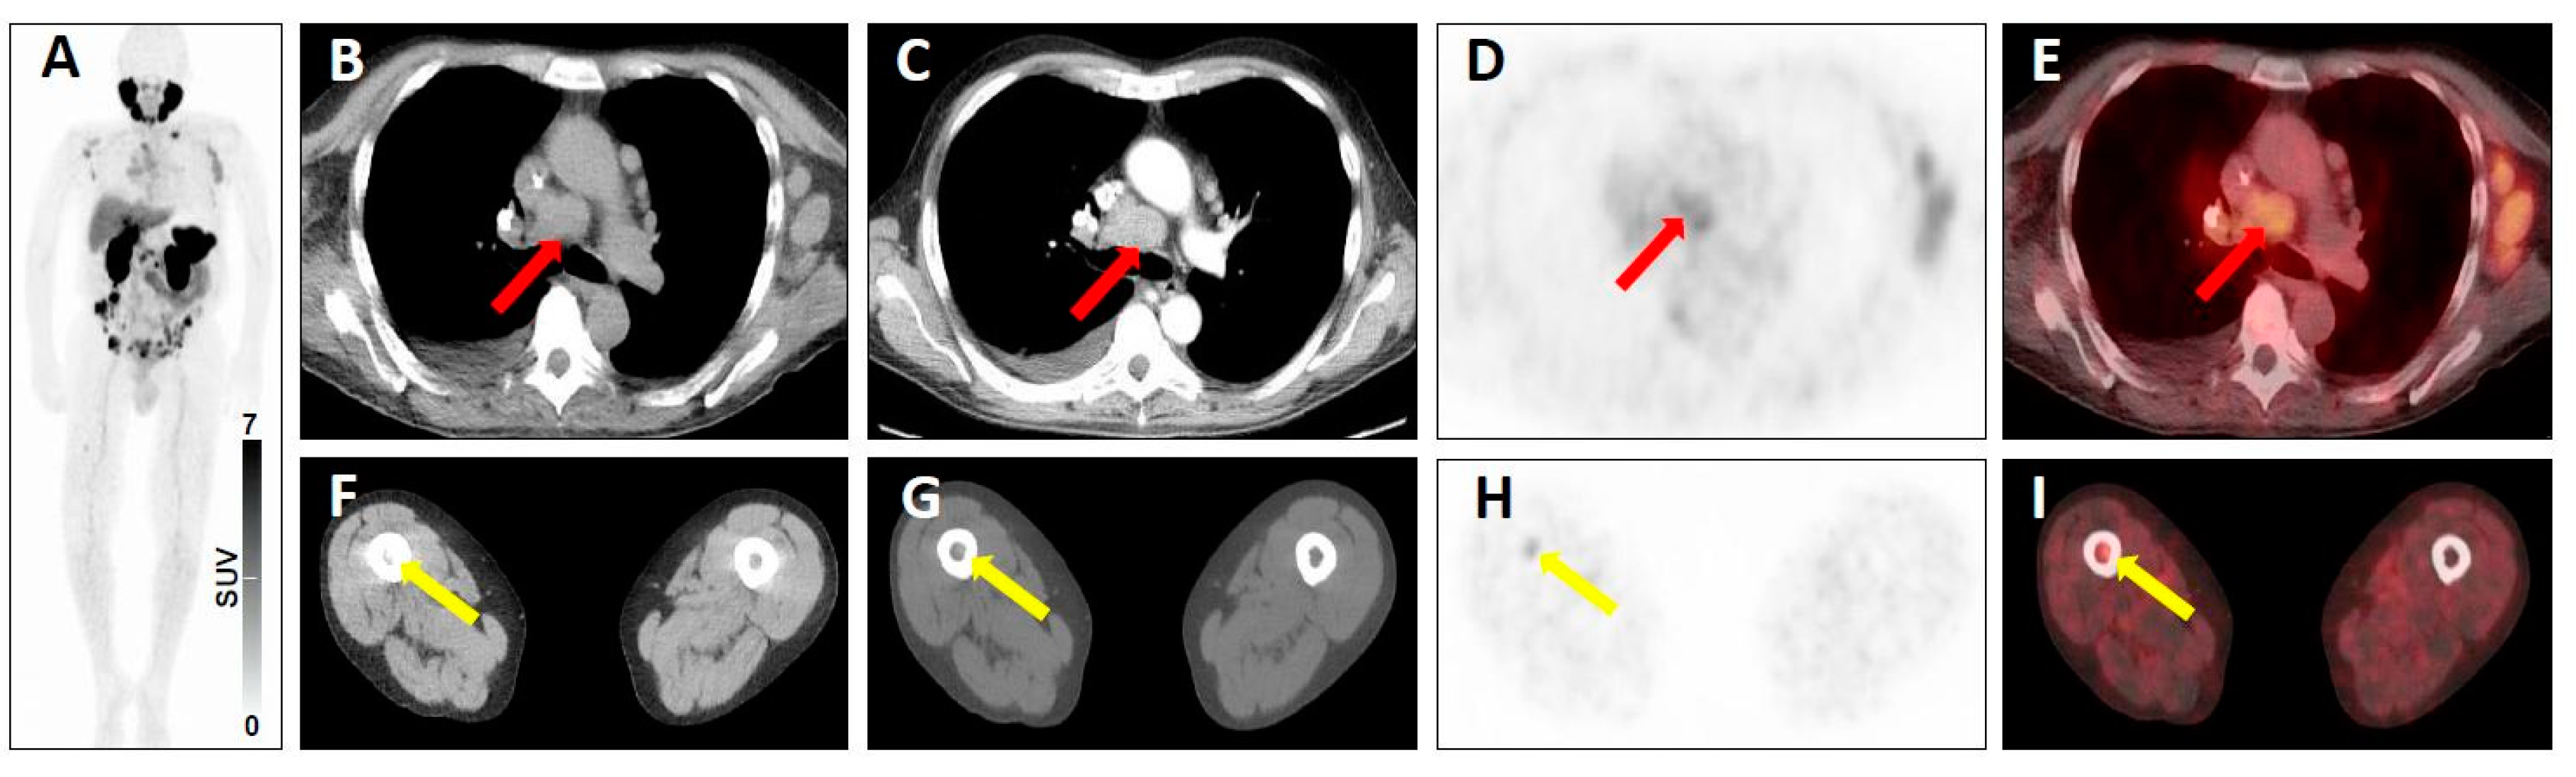

| 3C | - Intense breast uptake on SSTR-PET [20,21] - Intense uptake in the Musculus vastus lateralis [18] | - High level of radiotracer uptake in a lung nodule in a patient with low level of serum prostate-specific antigen [19] - Substernal thyroid nodule with radiotracer uptake (and without further work-up) [21,72] | |